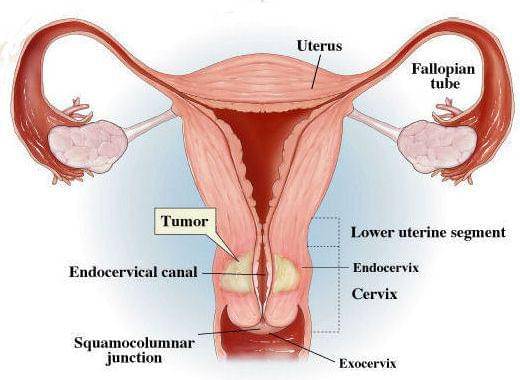

Medan, IDN Times – Kanker mulut rahim atau serviks berkembang pada sel dan jaringan yang ada di leher rahim. Penting mengetahui gejala awal kanker serviks. Sehingga kita bisa mengetahui kapan harus melakukan pemeriksaan ke dokter.

Kanker ini terjadi karena infeksi human papillomavirus atau HPV yang menular dari hubungan seksual, baik melalui oral maupun penetrasi. Selain itu, kanker serviks ada pada urutan nomor dua sebagai jenis kanker yang paling banyak terjadi di Indonesia.